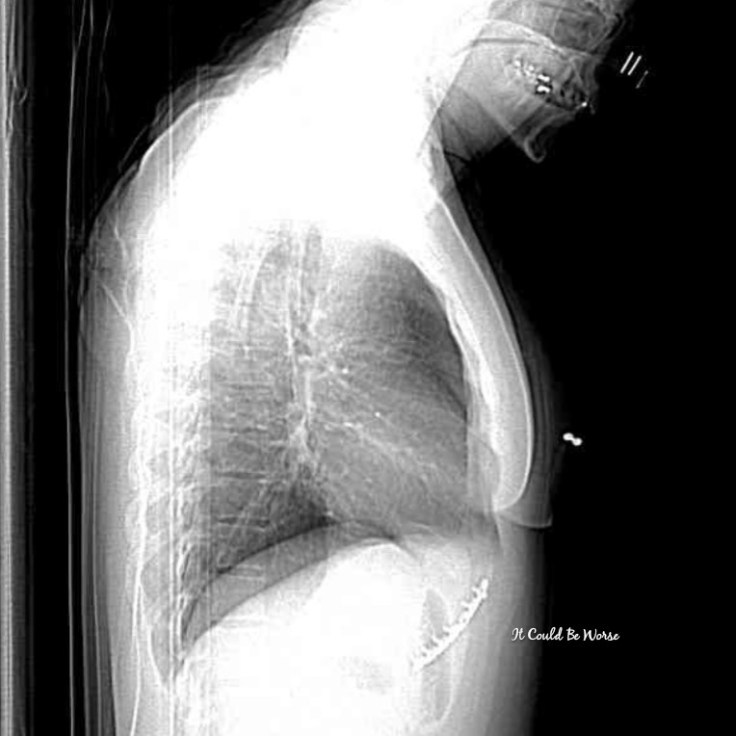

The positive is that I finally got imaging of the rib plate that had been placed in May for my Slipping Rib Syndrome at ribs 9-10. I was excited just to see what it looked like, to find out the details that I hadn’t been able to get with my online medical file – I hadn’t had imaging since before the procedure.

On Friday, I woke up coughing and with severe rib pain again, so I called my doctor to be seen. I wanted to try to avoid the emergency room and that chaos, so I scheduled to see her in an hour – I got lucky and she could see me that quickly. I didn’t even get out of pajamas for that appointment, and she ordered up an x-ray for my thoracic area.

She told me to start using my steroid inhaler again and try to rest. She didn’t see anything in the x-rays, granted, they never see anything – I know this because I lived with my fracture for a year, with multiple scans and imaging tests that all showed nothing.